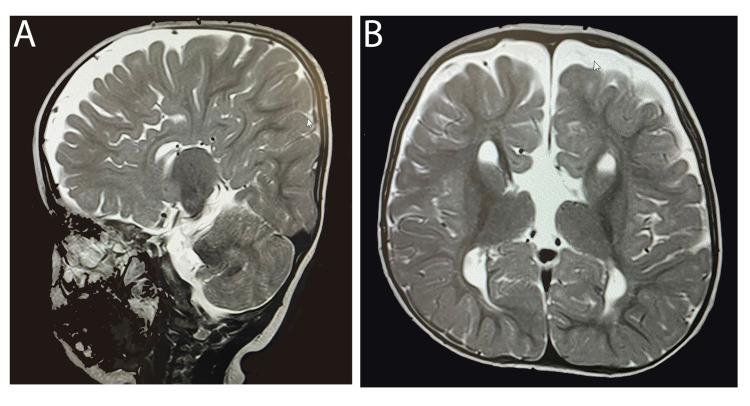

Donnai-Barrow syndrome (DBS) is a rare autosomal recessive hereditary disorder that affects a variety of body systems. One of the most common symptoms in DBS patients is severe bilateral sensorineural hearing loss. The objective of this report is to highlight the performance of such patients after receiving cochlear implants as a management of their hearing loss. We reviewed the medical records of two cousins diagnosed with DBS before and after cochlear implantation, with a particular focus on their auditory and language performance. After receiving the cochlear implant, both patients showed substantial progress in auditory and speech perception, as well as their intelligence quotients, allowing them to join mainstream schools. In conclusion, our findings showed that cochlear implantation can be considered an ideal approach for the management of DBS patients who suffer from bilateral sensorineural hearing loss.

唐纳-巴罗综合征(DBS)是一种罕见的常染色体隐性遗传性疾病,会影响多种身体系统。DBS患者最常见的症状之一是严重的双侧感音神经性听力损失。本报告的目的是强调此类患者接受人工耳蜗植入以治疗听力损失后的表现。我们回顾了两名被诊断为DBS的堂兄弟在人工耳蜗植入前后的病历,特别关注他们的听觉和语言表现。接受人工耳蜗植入后,两名患者在听觉和言语感知以及智商方面都取得了显著进步,使他们能够进入主流学校。总之,我们的研究结果表明,人工耳蜗植入可被视为治疗患有双侧感音神经性听力损失的DBS患者的理想方法。